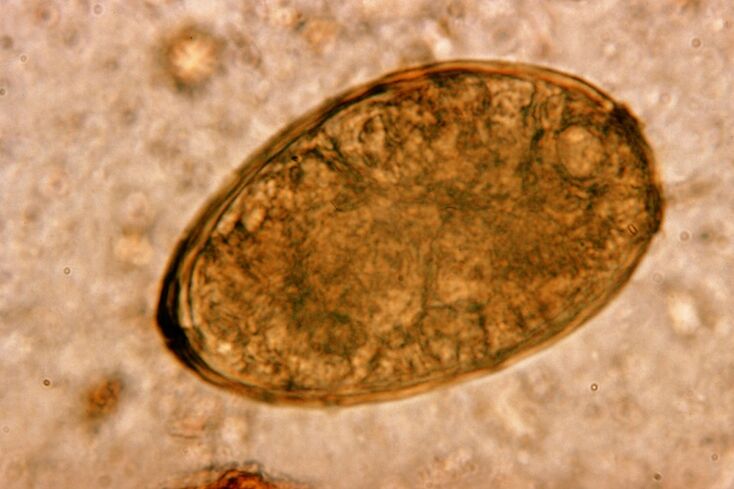

Bundlwalh, budugworms, langsung sareng ngahasilkeun dina peujit. Inféksi sareng aranjeunna lumangsung ngaliwatan endog anu asup kana awak nganggo tuangeun atanapi tina panangan sareng objek anu dianggo ku jalma anu katépa. Taneuh, buahan, sayuran, daging anu kirang masak sareng lauk - sadayana ieu tiasa ngenalkeun endog sayeuk kana awak manusa.

Ascariasis

Bunderan-buleud pisan nyebar, janten batuk ngalawan kasang tukang jéntrenis nyaéta fenomena khas. Inféksi sareng bulat anu lumangsung dina rute tradisional pikeun hminannemas. Ieu kalebet kontak sareng taneuh, tuang buah-buahan anu henteu dipedong sareng sayuran, sareng panangan kotor.

R lega bérésna nyababkeun masalah ku mékanis mangaruhan jaringan resks pernapasan. Ieu lumangsung dina fase mulmite parasit. Mékanisme sareng urutan dampak bulayworms dina sistem pernapasan manusa nyaéta kieu.

Sakali dina saluran certifiefinal, endog bulkworm, dina pangaruh énzim sorangan sareng jus nyerna, ngucurkeun cangkangna, berilari kana larva. Kiwari dimungkinkeun di ditukuh ku kamampuan pikeun nembus témbok peujit kana aliran getih. Sanggeus aranjeunna dibangkah ku getih dina awak awak - ngahontal ati, jantung, bayah, sareng saluran pernaparin.